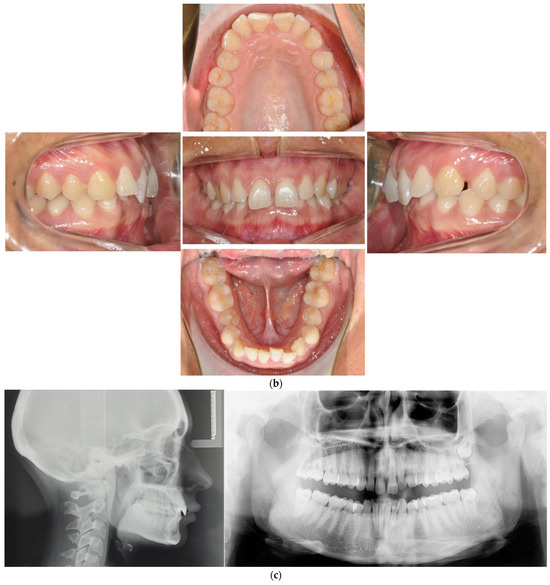

- Case 2: Class III with deep bite

4.2. Case 2: Class III with a Deep Bite